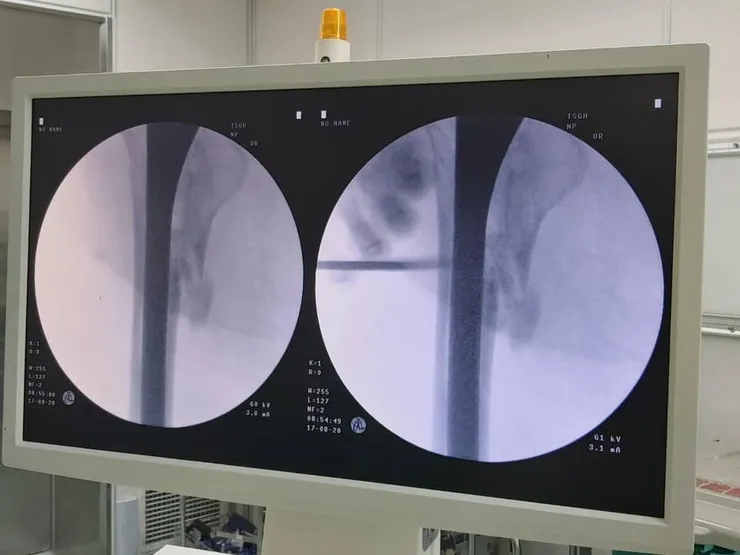

楊健福表示,大多數人認為膝關節退行性變是只在老年時才會出現的問題,但事實並非如此。楊健福接著說,軟骨磨損和撕裂不僅會導致膝關節退化,長期還會對韌帶和肌肉造成損傷,使膝關節發炎,從而導致不可逆的損傷,大多數患者為 4 至 50 歲的中年族巡。這證明了預防性治療和早期干預關節的重要性。此外,傳統的人工關節置換術常用於治療骨關節炎,膝關節退變問題可以得到有效解決,但也有其局限性。楊健福強調,人工關節畢竟是外來物,所以會有感染風險。

楊健福表示,骨關節運動損傷矯正很常見,不可逆損傷,關節型退行性跟變形式,病因難免,可以做運動。不過楊健福呼籲,雖然養成運動習慣可以避免,但太過劇烈的運動可能會造成運動損傷,運動損傷的四種主要類型,肌肉分離,肌肉拉傷,神經損傷和神經斷裂。楊健福強調,目前骨關節炎常見的治療方法為手術治療、藥物治療、物理治療這三種,不過這些治療方法效果不佳,常常是藥物治標不治本,未來則是幹細胞再生醫學時代。